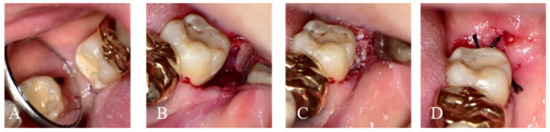

2.1.1. Immediate Graft

2.1.2. Delayed Graft